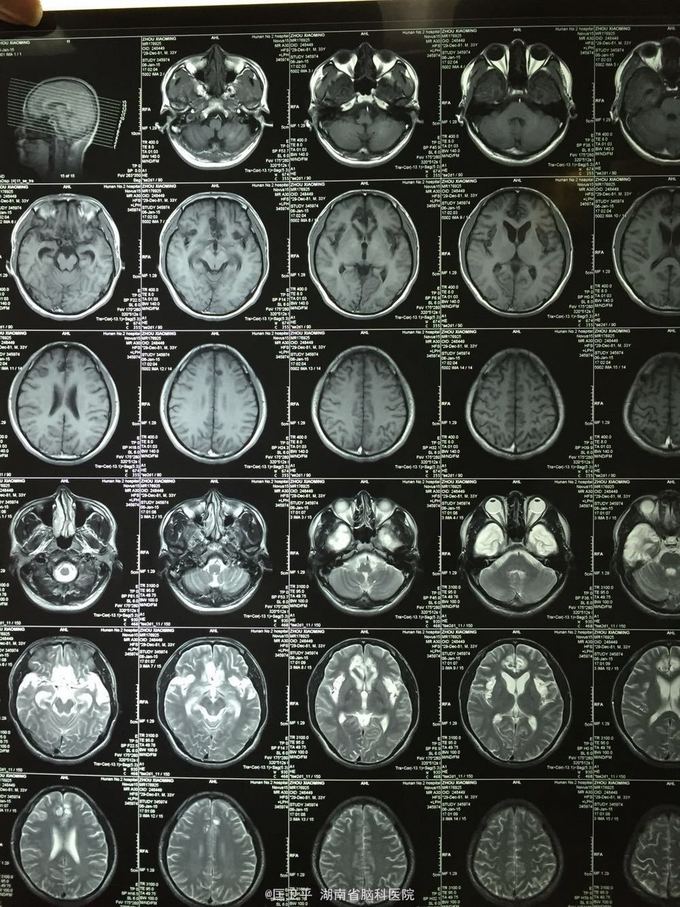

电击伤后智力低下,伤人毁物1年。 一年前在工地被电击伤昏迷,心跳呼吸停止,十几分钟后才有不规范的人工呼吸,持续约40分钟,心跳呼吸恢复。但患者智力低下,远近记忆很差,疑人害,伤人毁物严重,无法管理。

神清欠合作,五官无畸形,四肢活动正常,无神经定位体征。智能记忆很差,有被害妄想,有冲动攻击行为,无自知力,个人生活无法自理。

奥拉西坦,神经节䇞酯等护脑治疗; 丙戊酸镁、碳酸锂 稳定情绪; 奥氮平控制精神症状。 高压氧,经颅磁刺激治疗,心理治疗。